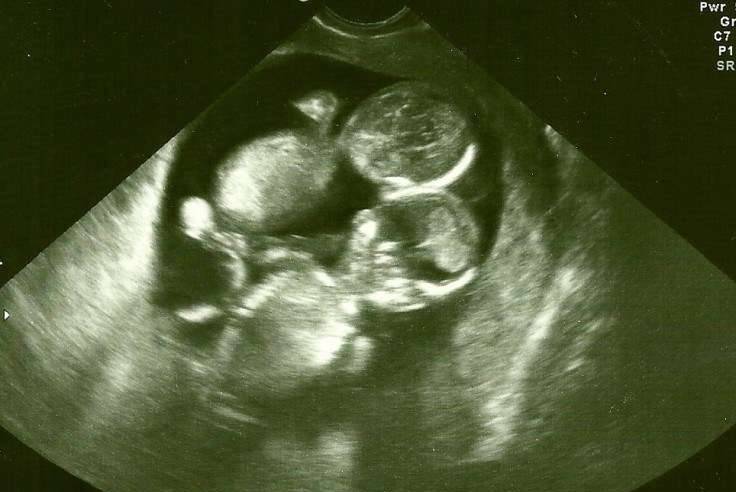

▼检查后,医生告知陈女士怀了双胞胎的喜讯,她听了兴奋不已;但很快医生话锋一转,遗憾表示宝宝是连体婴,这如同一个晴天霹雳打在陈女士身上,她想到自己好不容易才怀了这个身孕,如今却…想着想着就掉下了眼泪。

医生看到这个景象也不免吃惊,因为他很确定在照超音波的时候,2个宝宝是连在一起的;后来经过他的反覆猜测,才知道也许是照的时候,两个宝宝紧紧抱住了彼此,才会看起来像连体婴呢!